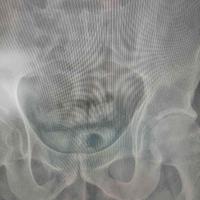

骶骨病变,腰骶固定

查看图片需登陆

骶骨病变,腰骶固定...

由 medjpg 发表于 2026-03-24 22:32